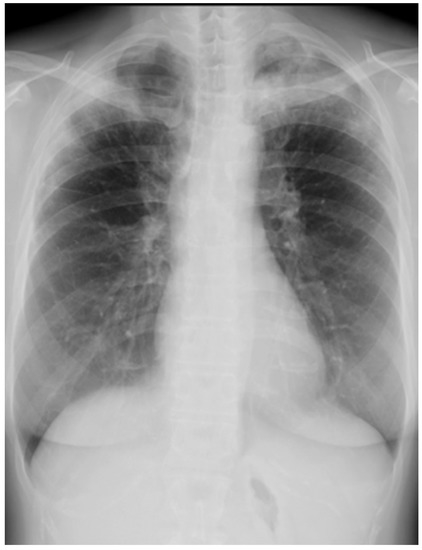

On arrival at our hospital, his blood pressure, pulse rate, and oxygen saturation were normal; however, his body temperature was 37.7 °C. The patient’s respiratory rate was 18 breaths/min. Chest auscultation revealed coarse crackles throughout the left lung field. A chest X-ray showed consolidation in the left lung field. (Figure 3) A chest CT scan showed consolidation in the entire left lung field and leftward deviation of the mediastinum, due to contractile changes. A small area of consolidation was seen just below the peripheral pleura in the right upper and middle lobes. (Figure 4) His blood tests showed leukocytosis (18,300/μL), eosinophilia (26.5%), and high C-reactive protein levels (18.12 mg/dL). KL-6 and SP-D levels were normal. Tests for beta-D-glucan, aspergillus antigen, interferon-gamma release assays, antineutrophil cytoplasmic antibody, antinuclear antibody, anti-aminoacyl-tRNA synthetase antibody, Anti-Scl-70 antibody, and anti-cyclic citrullinated peptide antibody were all negative. The PCR test for coronavirus disease 2019 was negative.

Figure 3. Chest X-ray of a 59-year-old man with dyspnea. It showed consolidation throughout his left lung field.